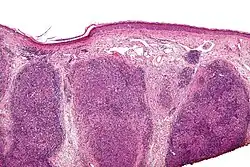

Low magnification micrograph of a lymphoepithelioma-like carcinoma showing the characteristic squamoid nests in association with clusters of lymphocytes. H&E stain.

Lymphoepithelioma-like carcinoma (LELC) is a medical term referring to a histological variant of malignant tumor arising from the uncontrolled mitosis of transformed cells originating in epithelial tissue (or in cells that display epithelial characteristics) that bear microscopic resemblance to lymphoepithelioma (nasopharyngeal carcinoma).

There is considerable variation in the classification of LELC—while it is perhaps most commonly considered a subtype of squamous cell carcinoma, it can also be classified as a form of large cell carcinoma (i.e. when occurring in the lung),[1] and can be considered as a separate, unique entity.[2]